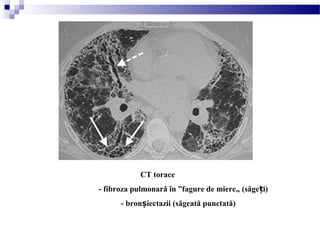

CT torace

- fibroza pulmonară în ”fagure de miere„ (săge i)ț

- bron iectazii (săgeată punctată)ș